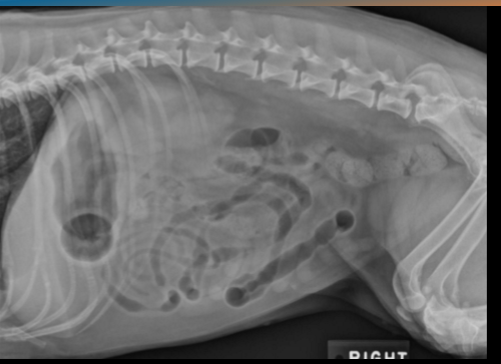

Identify the kidneys and bladder

A

Label the kidneys and bladder